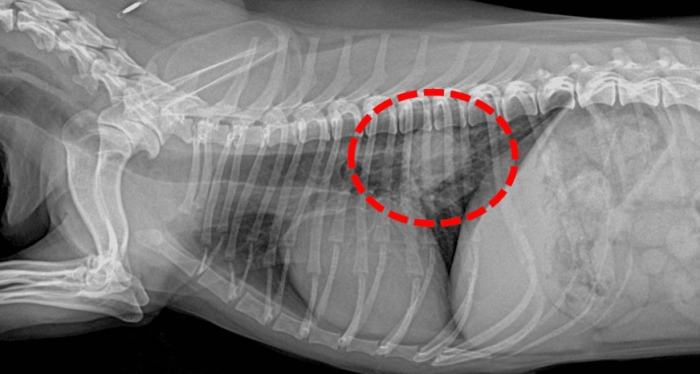

診斷過程通常需要多管齊下。獸醫可能會先聽診,然後建議做X光或超音波。X光是最基本的工具,可以看肺部的陰影變化。但如果腫瘤很小,X光可能看不出來,這時就需要進階檢查如CT掃描。

| 影像學檢查 | X光、超音波 | 查看肺部有無異常陰影 |

| 進階診斷 | CT掃描、活檢 | 確認腫瘤位置和類型 |